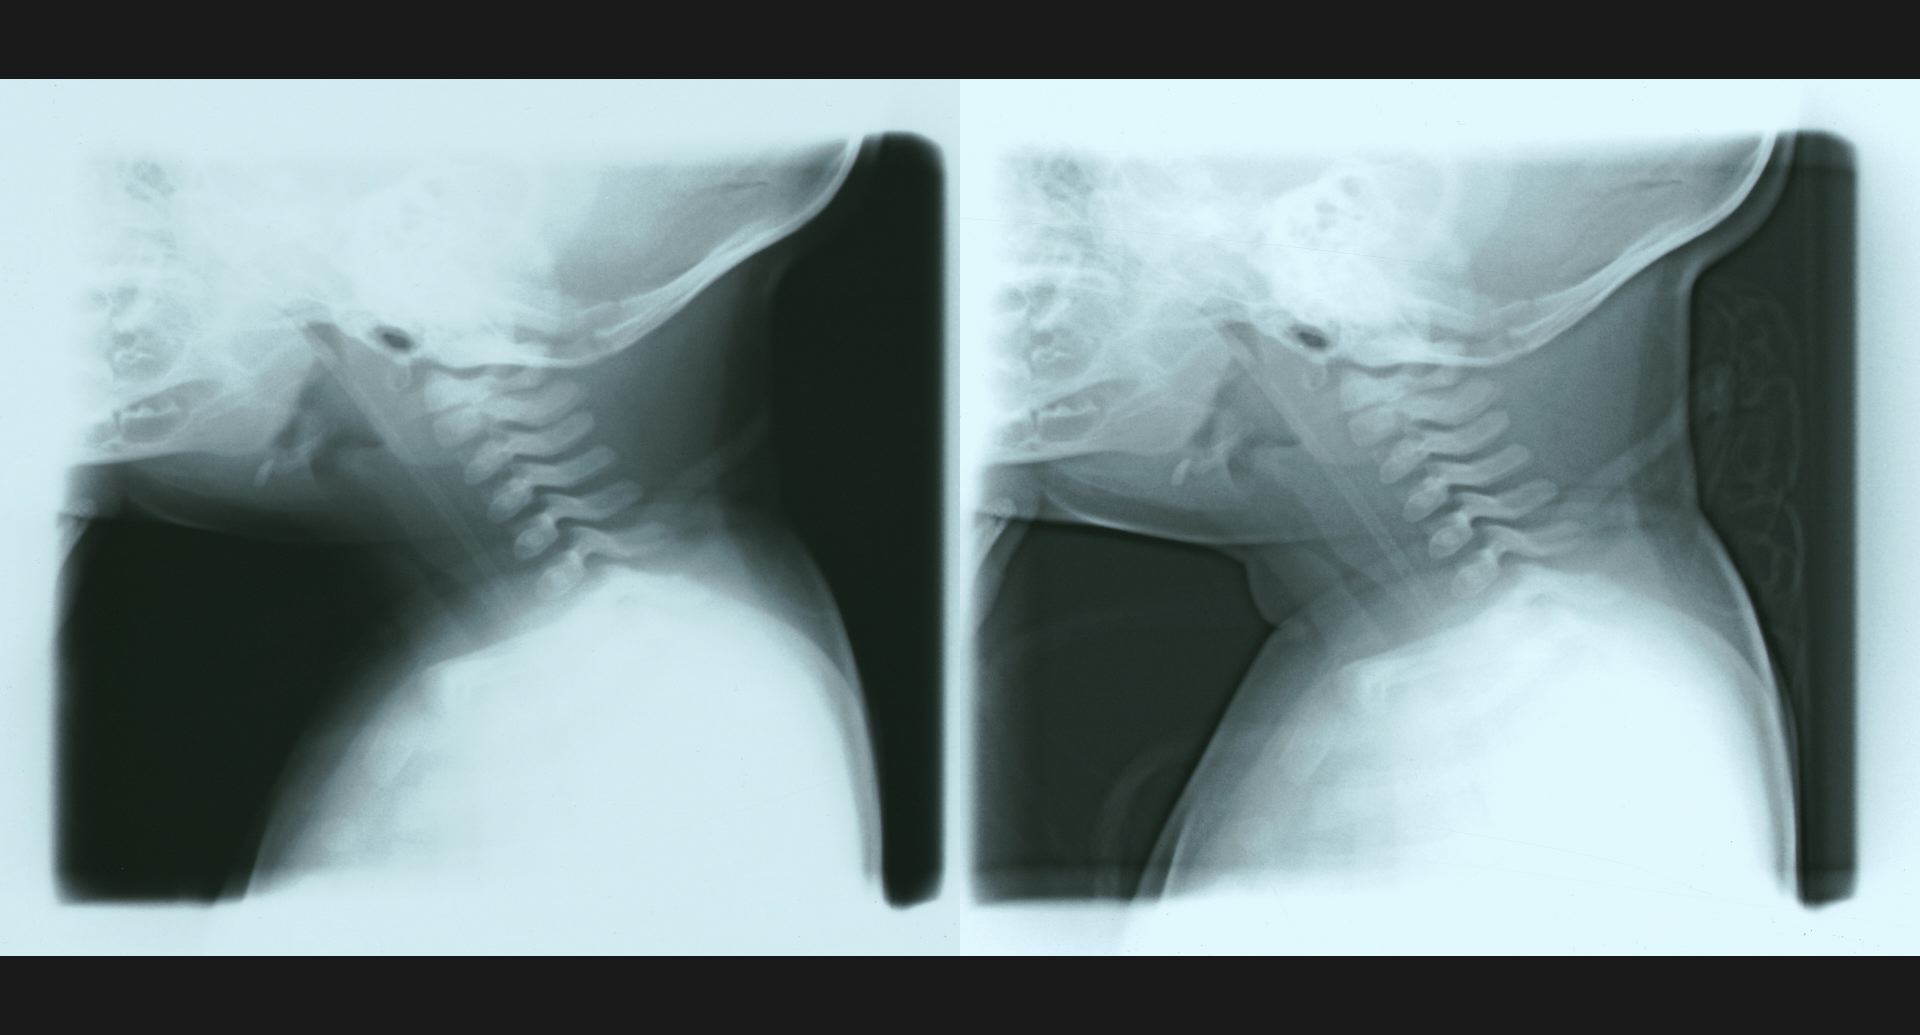

fig.11(59KB) :IVC stenosis (cavography), lateral view

collateral vein。狭窄。